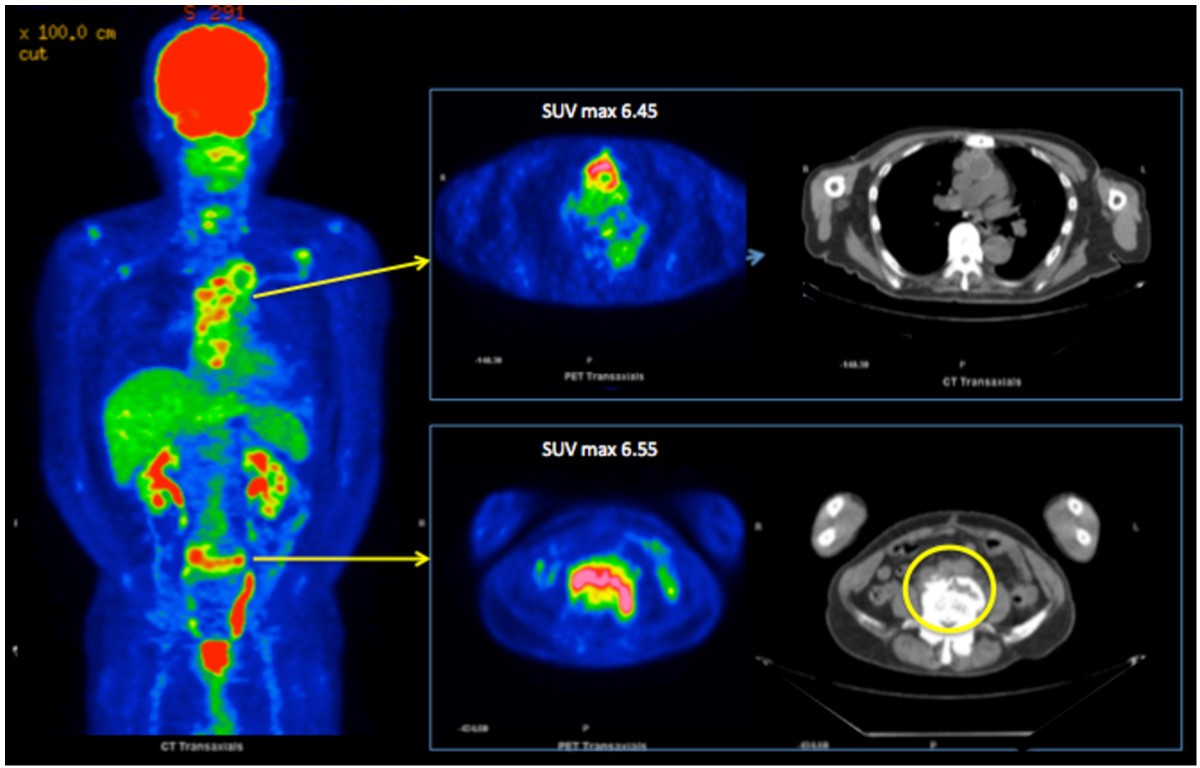

PET/CT scan 10/28/21 Multifocal hypermetabolic mixed lytic and Pet Ct Scan For Infection Combining a pet scan with an mri or ct scan can help make the images easier to interpret. At left is a ct scan, while the center image is a pet scan. The image on the right is. Pet scans play can play an important role in the detection of infections, offering a view of the body’s metabolic activity. Learn. Pet Ct Scan For Infection.

Pet Ct Scan For Infection . Combining a pet scan with an mri or ct scan can help make the images easier to interpret. Positron emission tomography, also called pet imaging or a pet scan, is a diagnostic examination that involves getting images of the. At left is a ct scan, while the center image is a pet scan. A positron emission tomography (pet) scan detects abnormal cell metabolism to diagnose cancer, heart disease, and brain disorders. The image on the right is. [ 18 f] has good. Pet scans play can play an important role in the detection of infections, offering a view of the body’s metabolic activity. For example, combining a pet scan with a ct scan (pet/ct) can provide more comprehensive information. A number of practical advantages make fdg pet/ct one of the procedures of choice for assessment of patients with infection and inflammation. Learn about the benefits of a pet scan and.

For example, combining a pet scan with a ct scan (pet/ct) can provide more comprehensive information. Learn about the benefits of a pet scan and. At left is a ct scan, while the center image is a pet scan. [ 18 f] has good. Positron emission tomography, also called pet imaging or a pet scan, is a diagnostic examination that involves getting images of the. The image on the right is. Combining a pet scan with an mri or ct scan can help make the images easier to interpret. Pet scans play can play an important role in the detection of infections, offering a view of the body’s metabolic activity. A positron emission tomography (pet) scan detects abnormal cell metabolism to diagnose cancer, heart disease, and brain disorders. A number of practical advantages make fdg pet/ct one of the procedures of choice for assessment of patients with infection and inflammation.